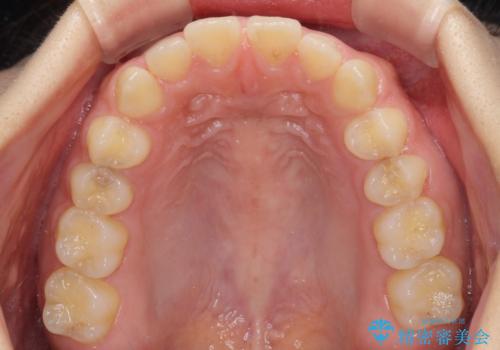

- 後戻りによる上下前歯の隙間を気にして来院された患者様です。

歯列不正はそれほど大きくなかったため、インビザライン・ライトを用いて矯正治療を行うこととしました。

無理のないペースで治療を進め、9ヶ月で終えることができました。